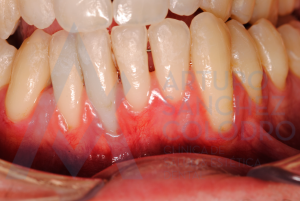

Estas son las imágenes obtenidas de exploración intraoral inicial: